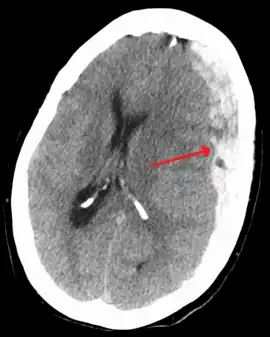

| Subdural hematoma as marked by the arrow with significant midline shift | |

On a CT scan, subdural hematomas are classically crescent-shaped, with a concave surface away from the skull. However, they can have a convex appearance, especially in the early stages of bleeding. This may cause difficulty in distinguishing between subdural and epidural hemorrhages. A more reliable indicator of subdural hemorrhage is its involvement of a larger portion of the cerebral hemisphere. Subdural blood can also be seen as a layering density along the tentorium cerebelli. This can be a chronic, stable process, since the feeding system is low-pressure. In such cases, subtle signs of bleeding—such as effacement of sulci or medial displacement of the junction between gray matter and white matter—may be apparent.